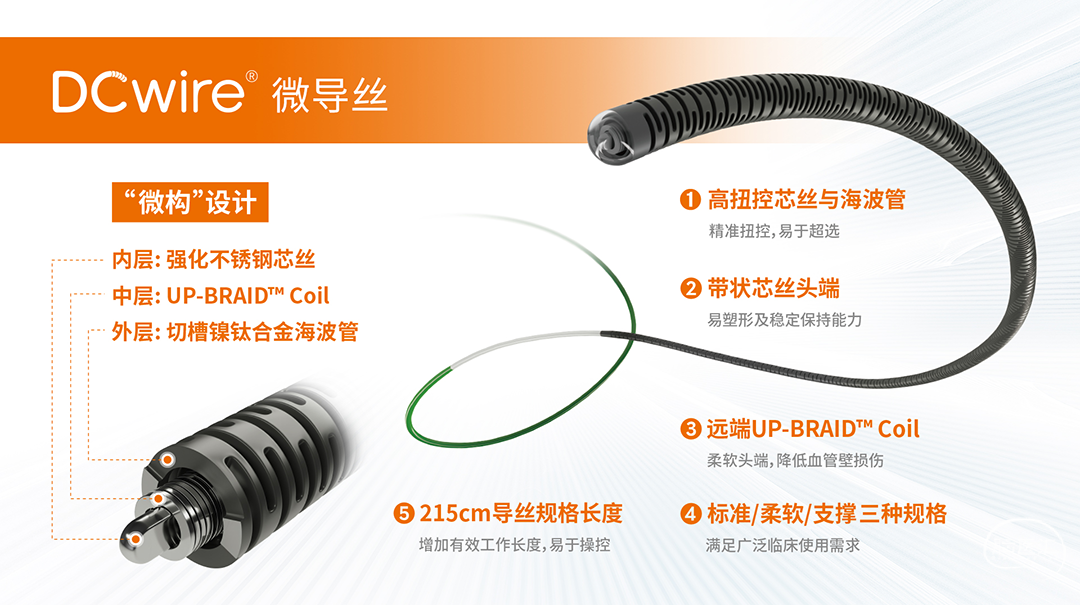

术中涉及介入器械选择

· 加奇生物 DCwire®微导丝

DCwire®微导丝迂曲路径下指引:经DCwire®微导丝指引跟进微导管通过大脑中动脉M1段闭塞病变段并超选至M2段分支,微导管到位造影提示真腔。

交换315cm DCwire®微导丝:迂曲路径下沿微导丝送入扩张球囊到位,球囊到位后由远及近分段扩张。

迂曲路径下DCwire®微导丝指引微导管到位。

沿DCwire®微导丝球囊扩张后送入微导管,使用交换技术撤出微导丝并释放支架。